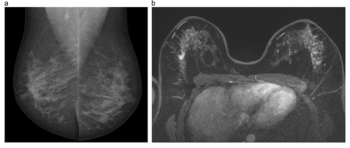

External validation testing revealed a deep learning combination of breast MRI, ultrasound and clinical factors had a 10 percent higher AUC for predicting axillary lymph node metastasis than sole use of MRI- or ultrasound-based deep learning models in patients with breast cancer.